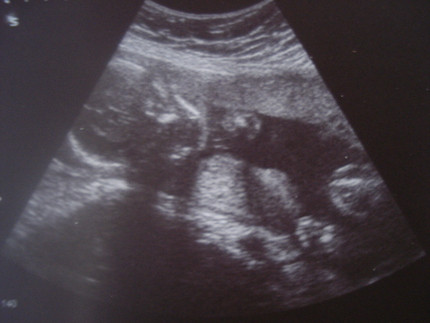

Беременность 22 недели мальчик

Беременность 22 недели мальчик 115 фото